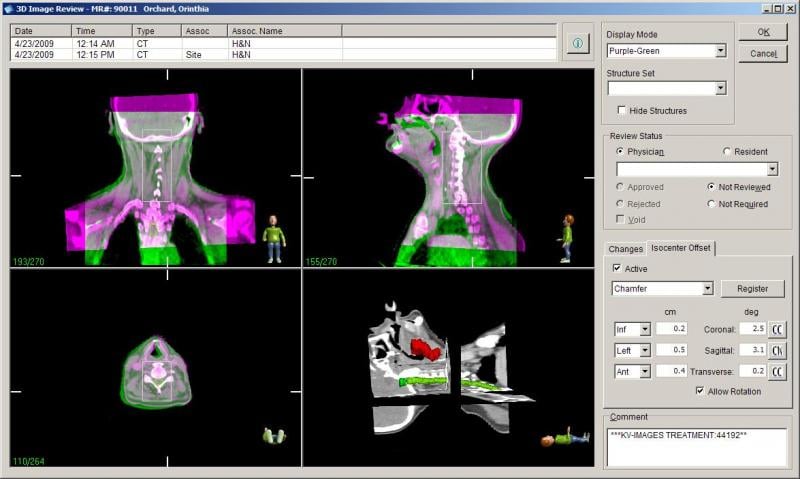

Treatment planning systems are at the heart of radiation therapy (RT) and the key to improved patient outcomes. Once image datasets are loaded and the tumors are identified, the systems develop a complex plan for each beam line route for how the therapy system will deliver radiation.

The Radiation Oncology Department at Auckland City Hospital, New Zealand, has made great strides in boosting efficiency over the last few years, while taking quality of treatment to new levels. It’s a shift in which technology has played a significant role. Today, the department is a pioneer of adaptive therapy. It also boasts one of largest VMAT programs in Australasia and operates a completely paperless workflow.